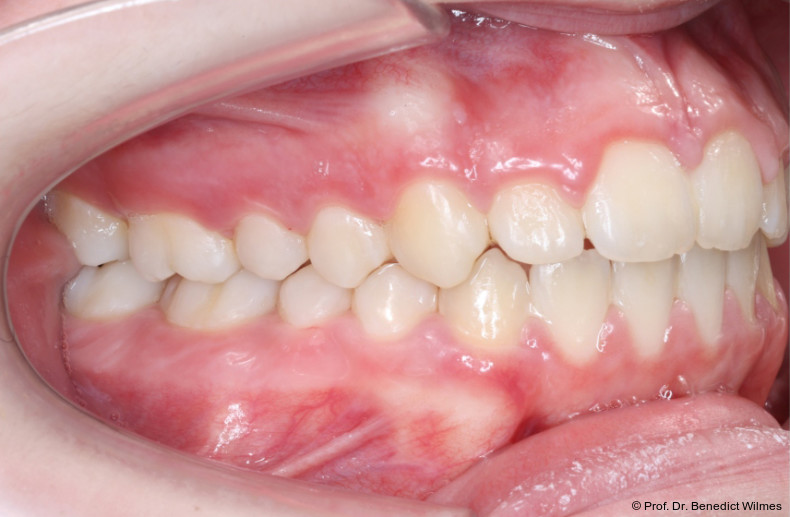

Eine 13-jährige Patientin stellte sich mit beidseitigem Kreuzbiss, einem anterioren offenen Biss und einer Angle Klasse II vor. Das viszerale Schluckmuster wurde mittels logopädischer Maßnahmen umgestellt, der offene Biss persistierte jedoch (Abb. 3a–l).